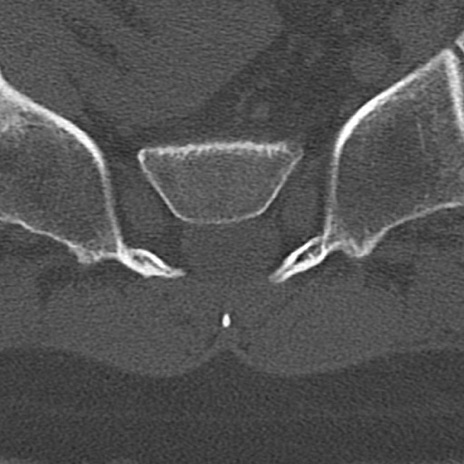

腰椎CT

横断像と矢状断像